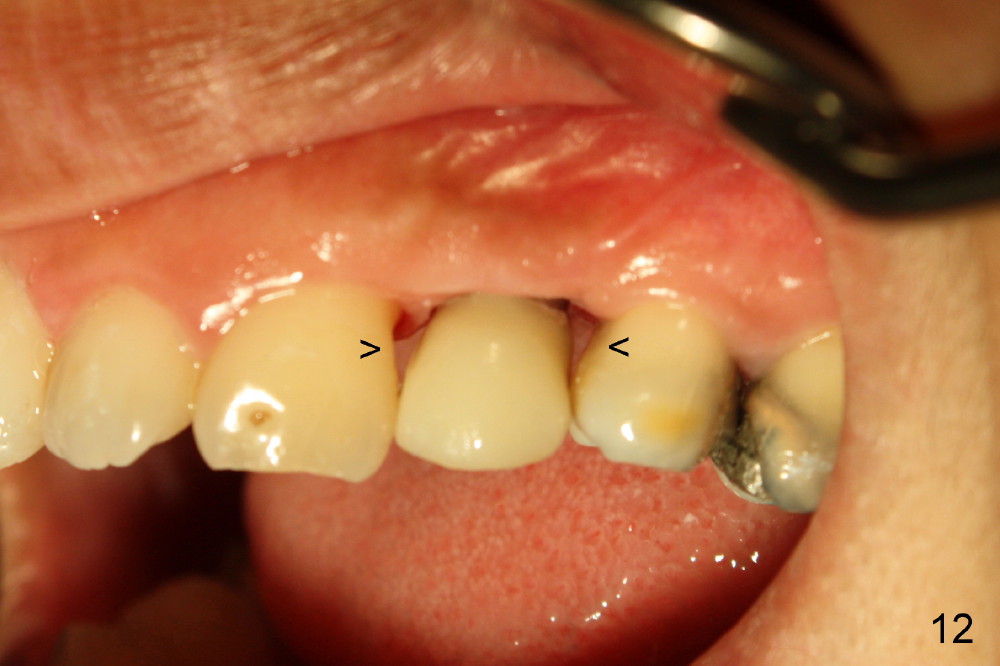

The closure of the socket involves raising and advancing both buccal and lingual flaps (Fig.10,11). When a crown is cemented, the patient is not pleased with recessive papillae (Fig.12 (arrowheads),13). It appears that flaps should be avoided to prevent cosmetic issue. Immediate implant is not enough for cosmetics; immediate provisional can close the extraction socket and support the papillae.